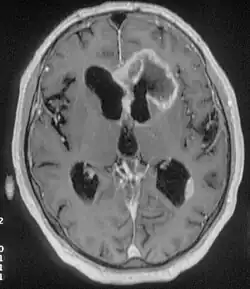

| Ressonância magnética de metástases de um cancro do pulmão no hemisfério cerebral direito . | |

Os tumores do cérebro secundários, ou metástases, são mais comuns que os tumores do cérebro primários.[2] Cerca de metade das metástases são provenientes do cancro do pulmão.[2] Os tumores cerebrais primários afetam por ano cerca de 250 000 pessoas em todo o mundo, o que corresponde a menos de 2% do total de casos de cancro.[3] Em jovens com idade inferior a 15 anos, os tumores do cérebro são a segunda principal causa de cancro, atrás apenas da leucemia linfoide aguda.[8]